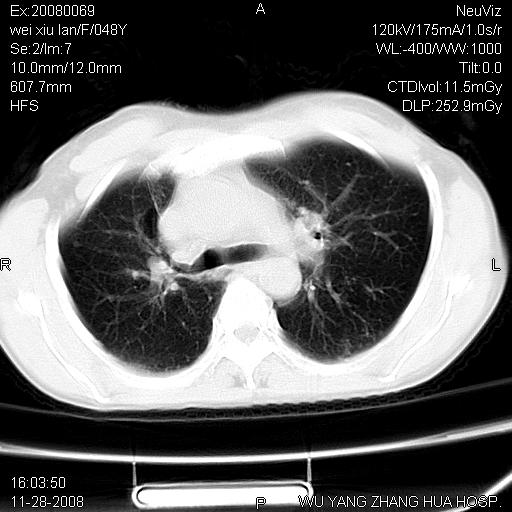

考虑 膈疝或食管裂孔疝或膈膨升,建议透视下吞钡观察明确

考虑左侧膈疝,建议作钡餐

膈疝或食管裂孔疝或膈膨升,建议透视下吞钡观察以进一步明确。